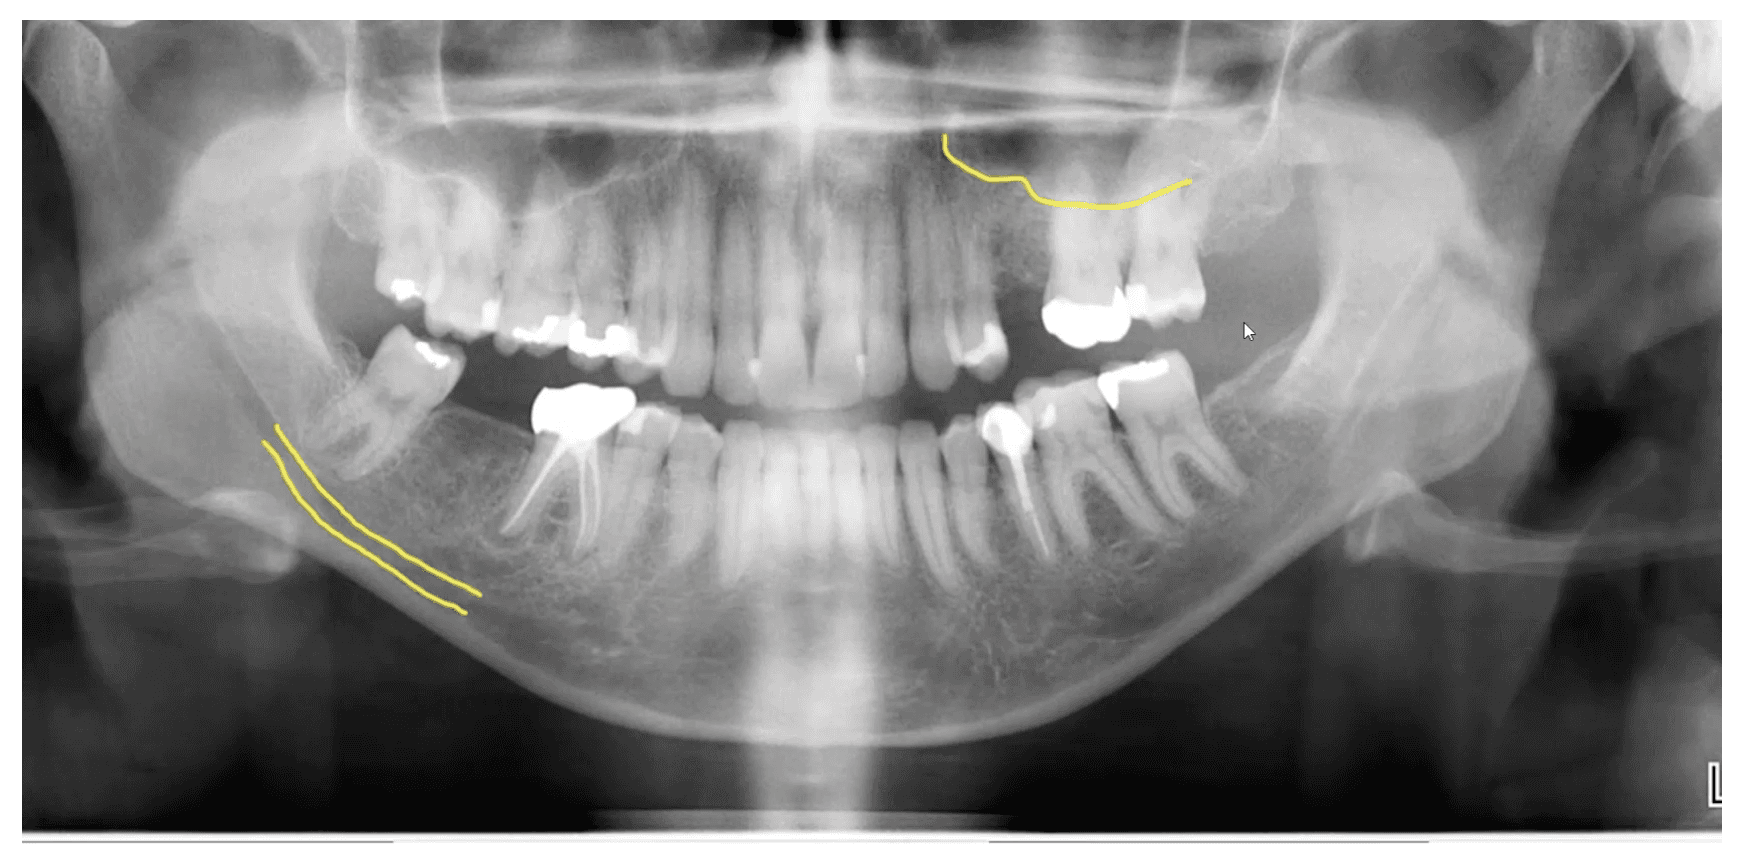

➡️ How to Plan on Pano and CBCT